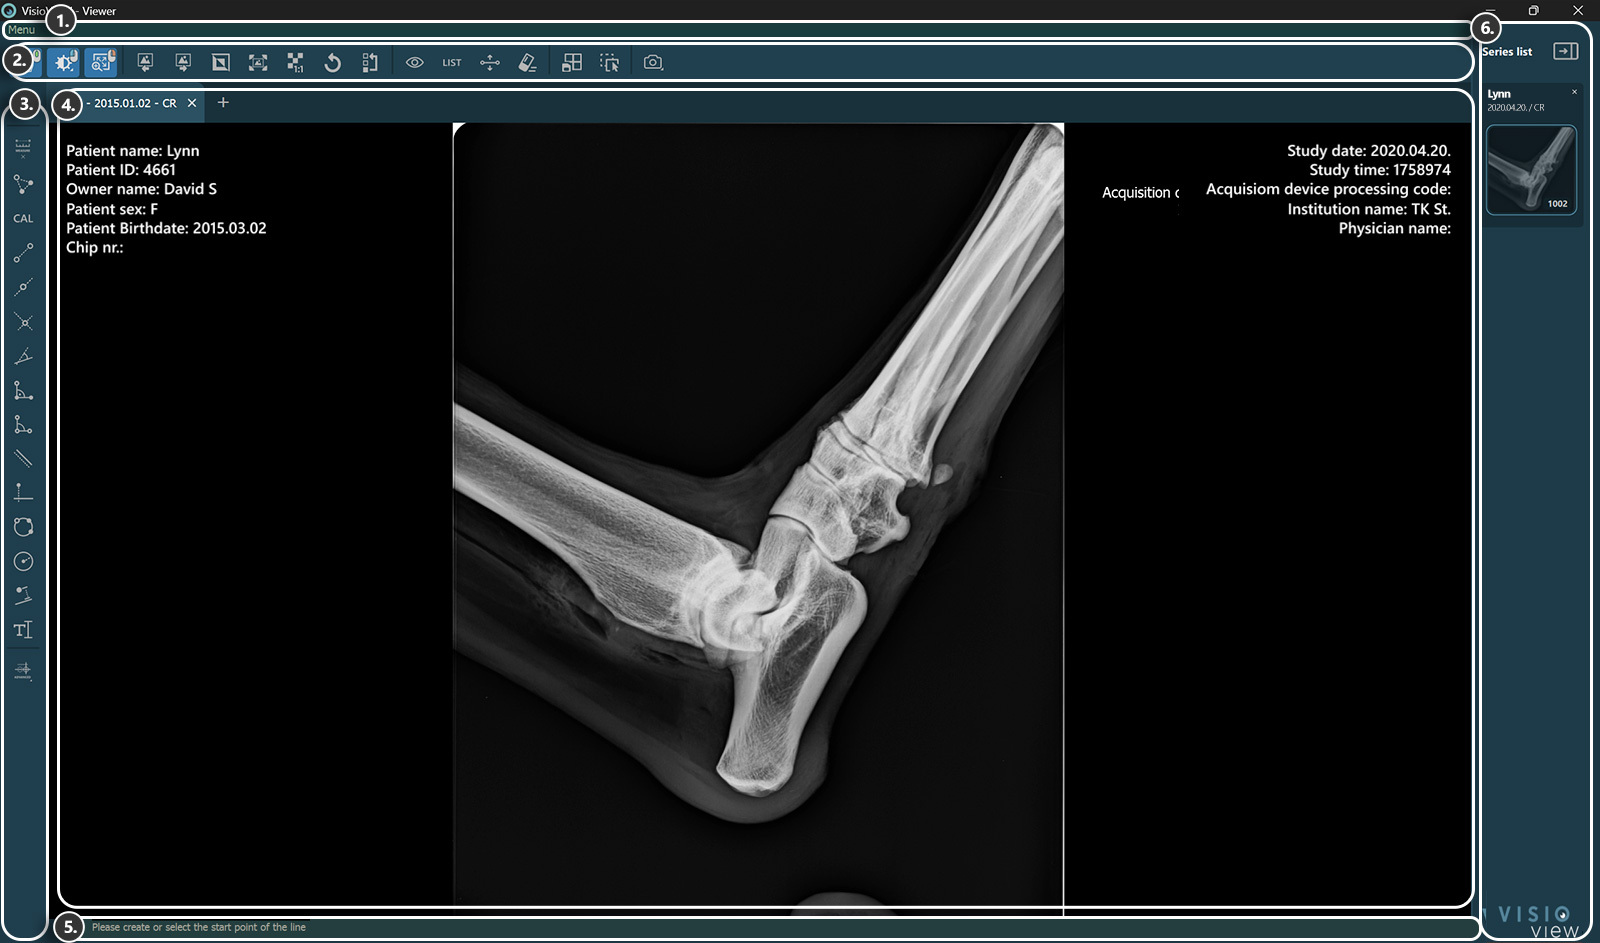

VisioVIEW - Viewer¶

The VisioVIEW Viewer¶

Sections of the VisioVIEW Viewer¶

The VisioVIEW Viewer consists of several sections, each tailored to a specific purpose. Below is a detailed description of each section.

Viewer Area¶

Patient information

Study information

Information Bar¶

Shows information or instructions about the currently selected tool.